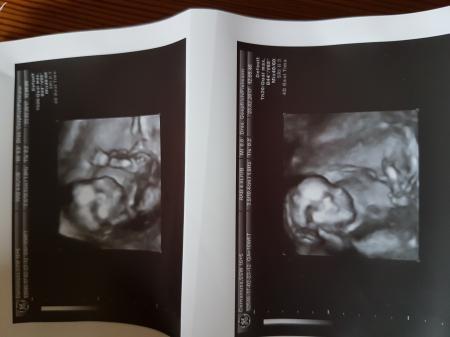

Zwergi ist jetzt knapp 13 cm lang und ca. 150g schwer. Gewunken hat es auch.... Nur zwischen die Beine durften wir nicht schauen. Schade, dass man hier keine Videos hochladen kann- habe eins bekommen Am 02.03. Habe ich den grossen zuckertest Am 09.03. Termin und am 28.03. Termin zum organscreening. Hier die Bildchen von Zwergi LG

Bild zu Zurück vom Fa..... - Forum für August - Mamis